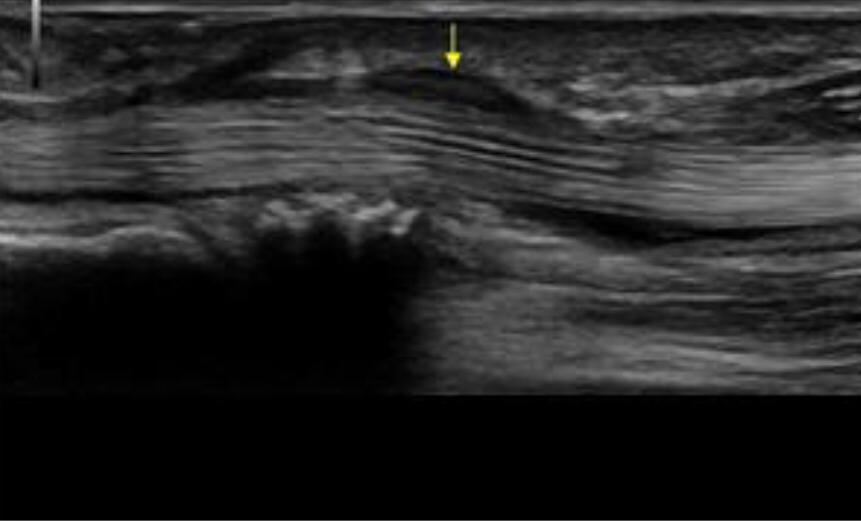

Thickening and hyper-vascularization of the A1 pulley are the hallmarks of trigger fingers on sonography. Other frequently observed features include distal flexor tendinosis and tenosynovitis.

The level of thickening can be variable with some authors suggesting the normal value being around 0.5 mm with thickening suggested when the diameter is over 1.1 mm.